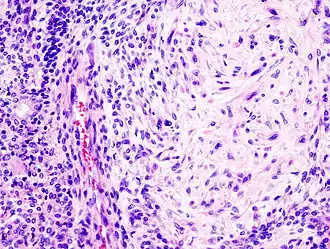

Histologicamente, o adenoma pleomórfico é um tumor tipicamente encapsulado e bem circunscrito.[1] Entretanto, a cápsula pode ser incompleta ou exibir infiltração por células tumorais.[1] Essa falta de encapsulação completa é mais comum nos tumores de glândula salivar menor, especialmente ao longo da porção superficial dos tumores do palato, abaixo da superfície epitelial.[7]

O tumor é composto de uma mistura de epitélio glandular e células mioepiteliais permeados por um estroma condromixoide em proporções variáveis.[1] Geralmente o epitélio forma ductos e estruturas císticas, ou pode ocorrer na forma de ilhotas ou cordões celulares.[1] As células mioepiteliais geralmente compõem uma grande porcentagem das células tumorais e exibem uma morfologia variável, podendo apresentar-se como células anguladas ou fusiformes.[1] Algumas células mioepiteliais são arredondadas e possuem núcleo excêntrico e citoplasma eosinofílico hialinizado, lembrando plasmócitos; estas células mioepiteliais plasmocitoides características são mais proeminentes nos tumores oriundos de glândulas salivares menores.[1]

O AP é caracterizado por metaplasia, seja ela adiposa, óssea, escamosa, sebácea ou mucinosa.[1] Em alguns tumores, é possível ver cristais de tirosina, aumento na celularidade e índice mitótico, e áreas ricas em células mioepiteliais.[1]